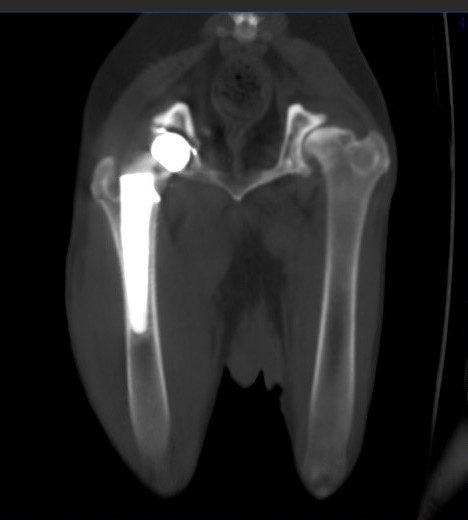

При остеоартрите объективным доказательством наличия хронической боли может служить снижение мышечной массы больной конечности (фото 4). При односторонних состояниях это можно проверить посредством ее сравнения с мышечной массой здоровой конечности. В билатеральных случаях, например при дисплазии тазобедренных суставов, наблюдается общее снижение мышечного тонуса в мышцах тазовых конечностей6.

Рентгенологически степень тяжести остеоартрита можно оценить по степени выраженности склероза субхондральной кости, инконгруэнтности суставных поверхностей, а также по количеству периартикулярных остеофитов и уменьшению суставного пространства, что свидетельствует о потере хрящевого слоя5. При прогрессировании остеоартрита развивается снижение плотности костных структур из-за неиспользования больной конечности. В тяжелых случаях остеоартрита может возникнуть анкилоз пораженного сустава.